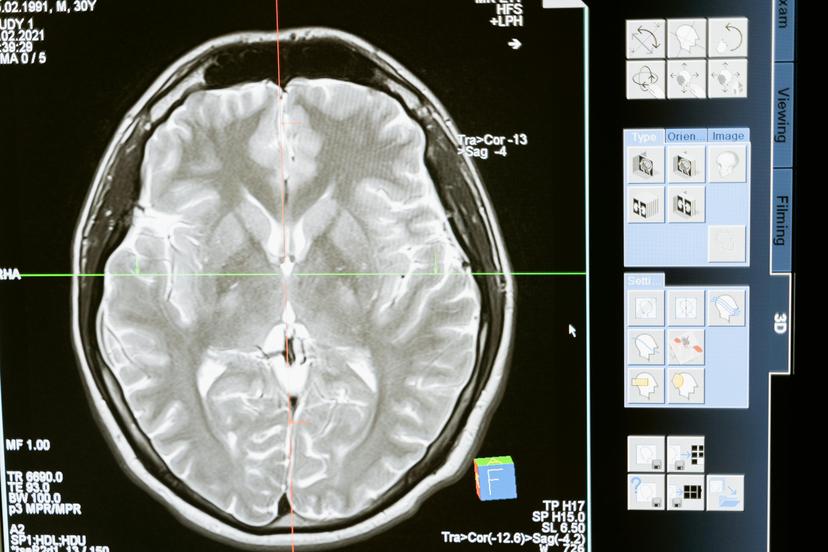

Ang epilepsy ba ay nakakagambala sa iyong buhay o ang buhay ng isang taong pinapahalagahan mo? Ang paghahanap ng tamang paggamot ay maaaring maging isang tunay na hamon, ngunit ang India ay maaaring magkaroon ng mga sagot na hinahanap mo. Sa mga makabagong pasilidad at ilan sa mga pinakamahusay na espesyalista sa mundo, ang India ay isang nangungunang destinasyon para sa pangangalaga sa epilepsy. Ang gabay na ito ay lalakad sa iyo sa mga nangungunang ospital, advanced na paggamot, at magagamit na pangangalaga sa eksperto. Isipin ang pamumuhay na may mas mahusay na kontrol sa mga seizure at isang pinahusay na kalidad ng buhay. Interesado sa kung paano makakatulong ang India? Sumisid sa komprehensibong mga pagpipilian sa paggamot ng epilepsy na magagamit.

Mga Opsyon at Pamamaraan sa Paggamot sa Epilepsy sa India